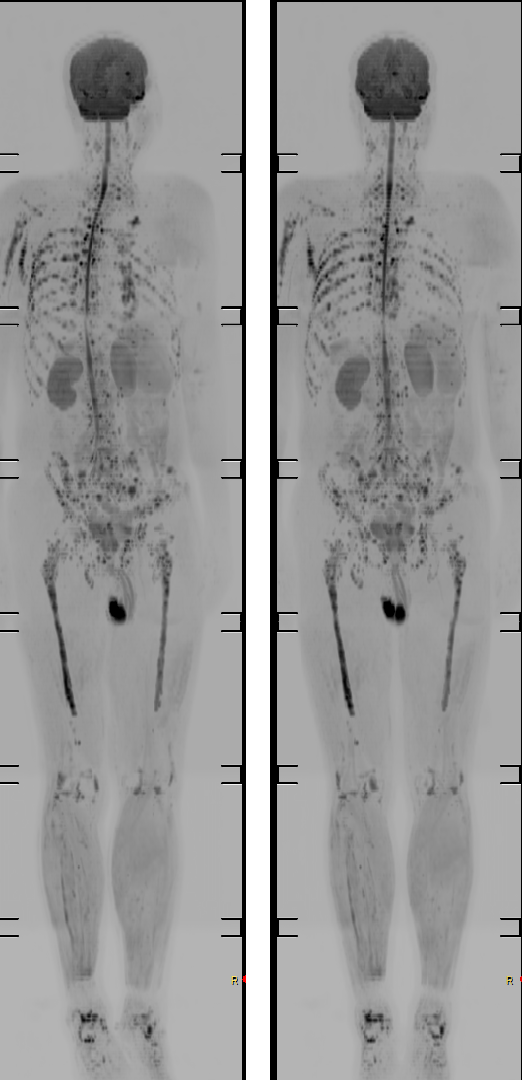

全身成像

全身成像是一种基于弥散的技术,可用于全身转移灶筛查、淋巴结转移筛查、发现明确恶性肿瘤指征寻找原发灶、血液恶性肿瘤病情监控、体检等。

DWIBS全身成像